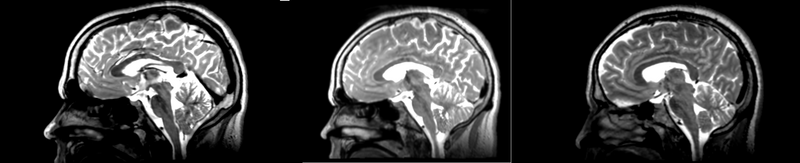

Original file(2,100 × 427 pixels, file size: 454 KB, MIME type: image/png)

Registration of two different subjects t2 images via the Bspline selection in the Register Images module.

current20:37, 22 April 2009Thumbnail for version as of 20:37, 22 April 20092,100 × 427 (454 KB)Rauscha (talk | contribs)Registration of two different subjects t2 images via the Bspline selection in the Register Images module.